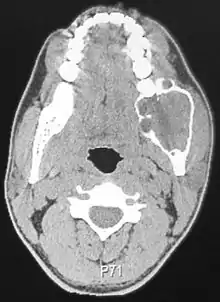

غالباً ما يصاحب الورم الأرومي المينائي وجود سن منطمر والأعراض تشتمل على تورم وتشوه في الوجه إذا كانت الحالة شديدة وألم في حال اصطدام الورم مع الأعضاء الاخرى وتخلخل في الأسنان وتقرحات ومرض دواعم السن وتحدث الأضرار في الفك السفلي والعلوي مع أن 75% منها تحدث في منطقة الفرع الصاعد وتتسبب في تشوهات غريبة وواسعة في الفك العلوي والسفلي ومن الممكن أن ينتشر الورم من الفك العلوي إلى جيوب الفك العلوي وفي سطح الأنف والأضرار المترتبة من المرض قد تتسبب في توسع القشور العظمية لأن معدل النمو البطيء للأضرار يمنح دواعم السن وقتاً لتكوين قشرة من العظام قبل توسع الأضرار وهذه القشرة العظمية تتصدع عند لمسها اثناء الفحص ويطلق على هذه الظاهرة بتكسر قشرة البيضة أو بالفرقعة ومن الخصائص التشخيصية المهمة هي أن الورم الأرومي المينائي يتم تشخيصه مبدئياً عن طريق الفحص بالأشعة ويجب التأكيد عليه بالفحص الهيستولوجي مثل الخزعة وفي الأشعة يكون الورم على شكل مكان مضيء في العظم بمختلف الأشكال والخصائص ففي بعض الأحيان يكون على شكل ضرر في مكان واحد ومحدد تحديداً دقيقاً بينما في الحين الآخر يكون في مناطق متعددة على شكل فقاعات صابونية ومن الممكن رؤية ارتشاف في جذور السن المتضرر في بعض الحالات ولكنه ليس بالأمر الغريب في الورم الأرومي المينائي حيث أن هذا المرض غالباً يتواجد في جزء الجسم الخلفي وفي زاوية الفك السفلي ولكن من الممكن كذلك أن تحدث في أي مكان سواءً الفك العلوي أو السفلي